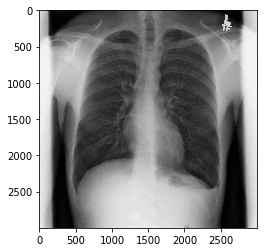

JIRAの胸部レントゲンをお借りします。

LEEとついているものは非圧縮画像という意味です。これを使います。

サンプル画像

plt.imshow(pixels,cmap="gray")#2つとも必要

plt.show()